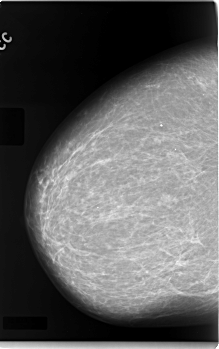

C_0083_1.LEFT_CC

LEFT_CC LINES 5864 PIXELS_PER_LINE 3840 BITS_PER_PIXEL 12 RESOLUTION 50 NON_OVERLAY